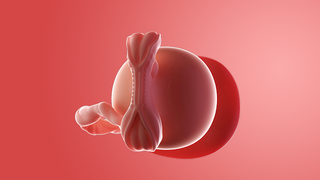

Your baby, or embryo, is about 2mm long (about the size of a poppy seed) and growing rapidly in your womb.

It's protected by an amniotic sac, which is filled with cushioning fluid, and attached to a tiny yolk sac that provides all the nourishment it needs.

The outer layer will later develop into the placenta and provide your baby with oxygen and nutrients.